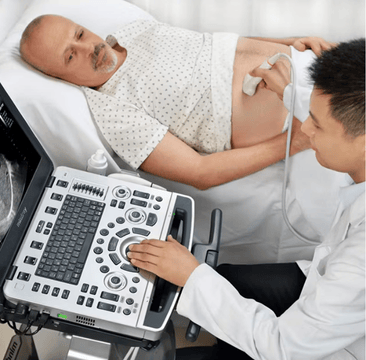

Ultrasound imaging continues to gain popularity and is quickly becoming the imaging modality of choice for a variety of clinicians, ranging from Emergency Medicine,?Critical Care, Radiology Labs, Vascular Labs, Ambulatory Care Centers, and more. Ultrasound is a cost-effective, real-time, and patient-friendly imaging alternative that can be done practically anywhere. These attributes have helped fuel ultrasoundŌĆÖs popularity across many medical fields and specialties. With ultrasound gaining popularity, it has raised questions about the many transducer types and offerings accompanying ultrasound machines.

Ultrasound transducers are used to image various body parts. To use an?ultrasound machine, you need to have a transducer that connects to the ultrasound machine. Once the transducer is connected to the ultrasound machine, the transducer is placed on the patient, and the clinician can visualize images of the patientŌĆÖs anatomy.